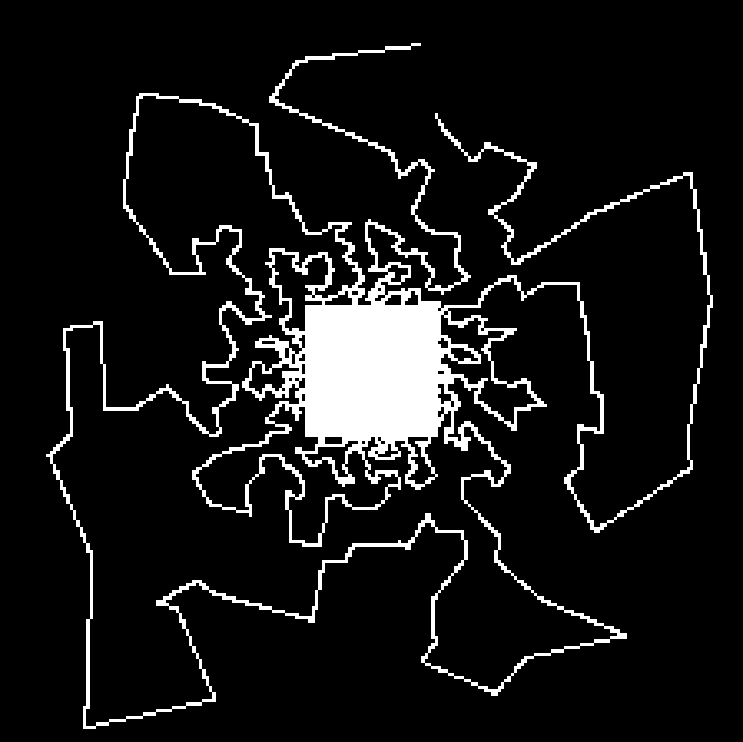

In this experiment, we considered a 2D -space () corresponding to an axial slice. We considered five sampling strategies, depicted in Fig. 2(first row): a classical EPI coverage used as reference (a); a TSP-based sampling trajectory parameterized using optimal control (b); two projected TSP-based trajectories, one with the same number of samples collected as in (b) () (c) and the other with the same scanning time as in (b) (62 ms) (d); a variable density spiral trajectory for comparison purpose in terms of time and sampling ratio (e).

As expected, the reconstruction results shown in Fig. 2(g,h) are really close, since the number of collected samples is the same, and the sampling densities are similar. However, in this comparison the gain in traversal time is significant (one half). In contrast, the longer and smoothed TSP depicted in Fig. 2(d) allows us to improve image reconstruction (1 dB gain) as illustrated by Fig. 2(i) while keeping the same acquisition time as in Fig. 2(b). For comparison purposes, we implemented spiral acquisition which consists of replacing steps (ii)-(iii) in the above mentioned sampling strategy by a spiral with density proportional to , projected onto the set of constraints. This strategy doubles the acquisition time (118 ms compared to 62 ms) whereas the acceleration factor was larger ( vs. ). In this experimental context (regridding and variable density spiral), the spiral is not appealing compared to EPI acquisition, since it is time consuming and degrades the image quality.

In each of these reconstructions, the major vessels can be recovered, although the smallest ones can only be seen for . Finally, the best compromise between acquisition time and reconstruction quality is achieved using the specific combination of TSP-based sampling and our projection algorithm onto the set of constraints shown in Fig. 2(d).

| (a) | (b) | (c) | (d) | (e) |

|---|---|---|---|---|

|

Sampling schemes

|

|

|

|

|

| ms () | ms () | ms () | ms () | ms () |

| (f) | (g) | (h) | (i) | (j) |

|

Reconstructed slices

|

|

|

|

|

| Reference | PSNR = 25.9 dB | PSNR = 25.5 dB | PSNR = 26.9 dB | PSNR = 26.8 dB |